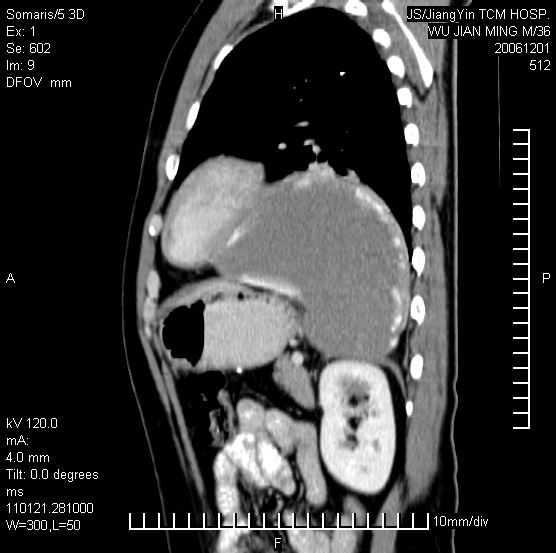

以下是引用dyqct在2006-12-1 21:17:00的发言:[br]左心缘旁及后肋膈窦区见巨大椭圆形混杂密度肿块,周围见大小不等斑片状钙化,内部无强化,周围包膜轻度强化,心脏明显受压变形,即明显占位效应,肿块广基与心包、膈相连。肝、脾内、肝门见多数小结节状钙化影。[br]考虑:1、左心缘旁及后肋膈窦区慢性包裹性胸膜炎(结核性);[br] 2、肝、脾及肝门淋巴结核已钙化。[br]

以下是引用zrs在2006-12-2 17:28:00的发言:[br]肺内、肝脾内虽有钙化,但不支持结核性胸胸膜炎包裹,而支持寄生虫感染![br][br]

以下是引用zyx168在2006-12-2 10:10:00的发言:[br][br]肝脾肺内多发钙化灶